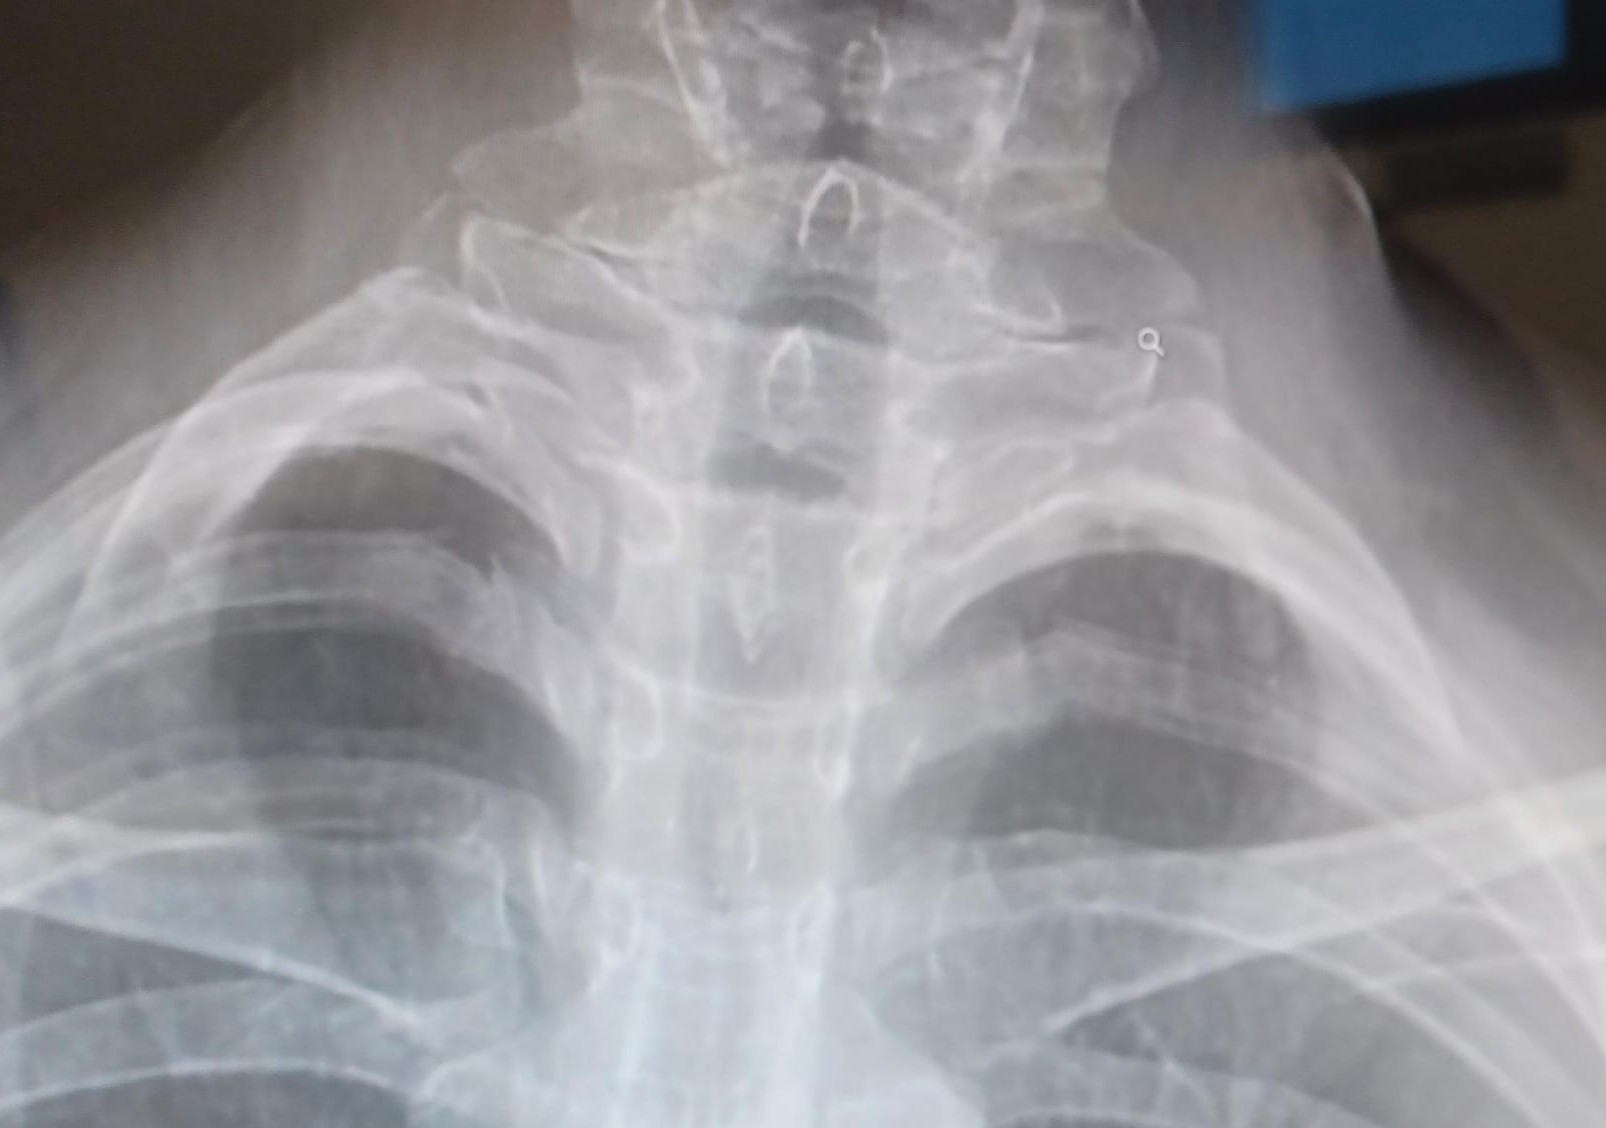

- Costella cervical. (Figures 2 i 3)

Figura 3: Costella cervical bilateral